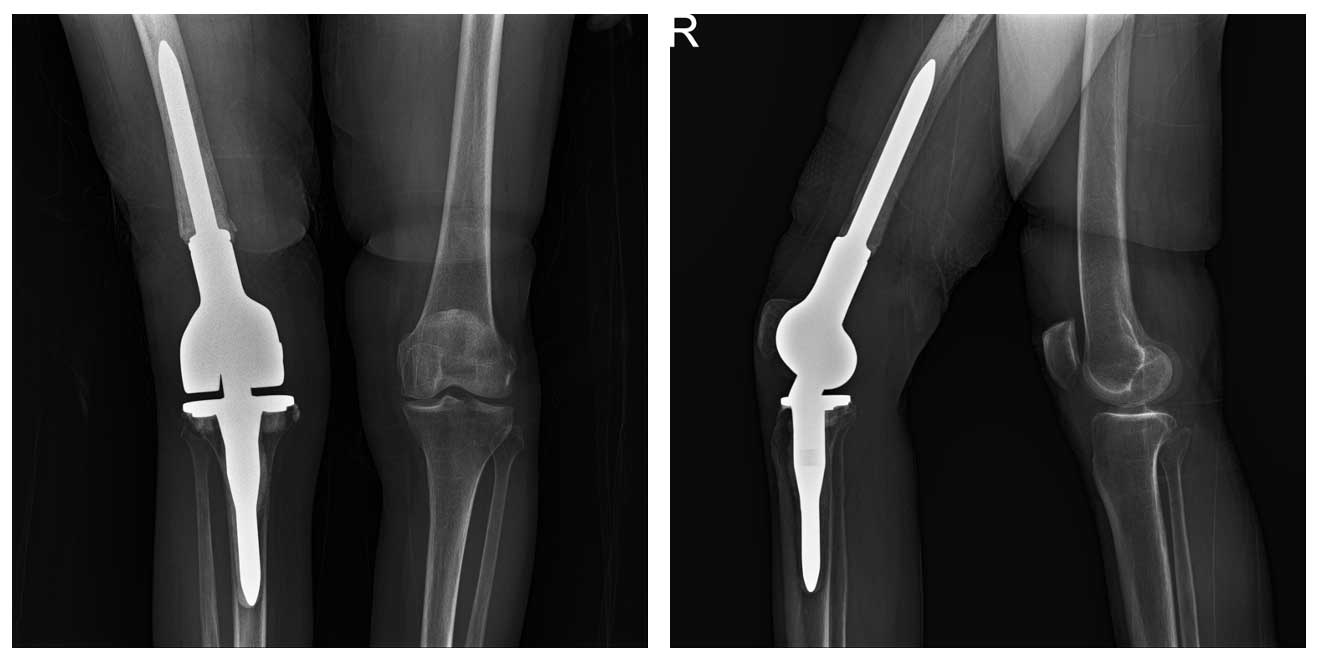

Ameliyat Sonrası: Röntgende rezeksiyon sonrası uygulanmış distal femur tümör protezi görülmekte.